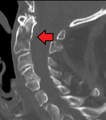

Type 3 odontoid fracture

- Type III Fracture - Extends through the vertebral body of the axis. This type can be stable or unstable and may require surgery.